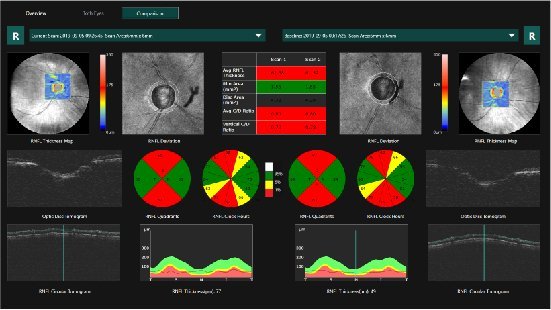

MOCEAN 4000

SLO-OCT e OCTA com VASCAN ADVANCE

O Mocean 4000 é configurado com os sistemas de imagens combinados SLO-OCT de ponta e o rastreador ocular baseado em SLO, uma plataforma poderosa para aplicações avançadas, como a angiografia OCT.